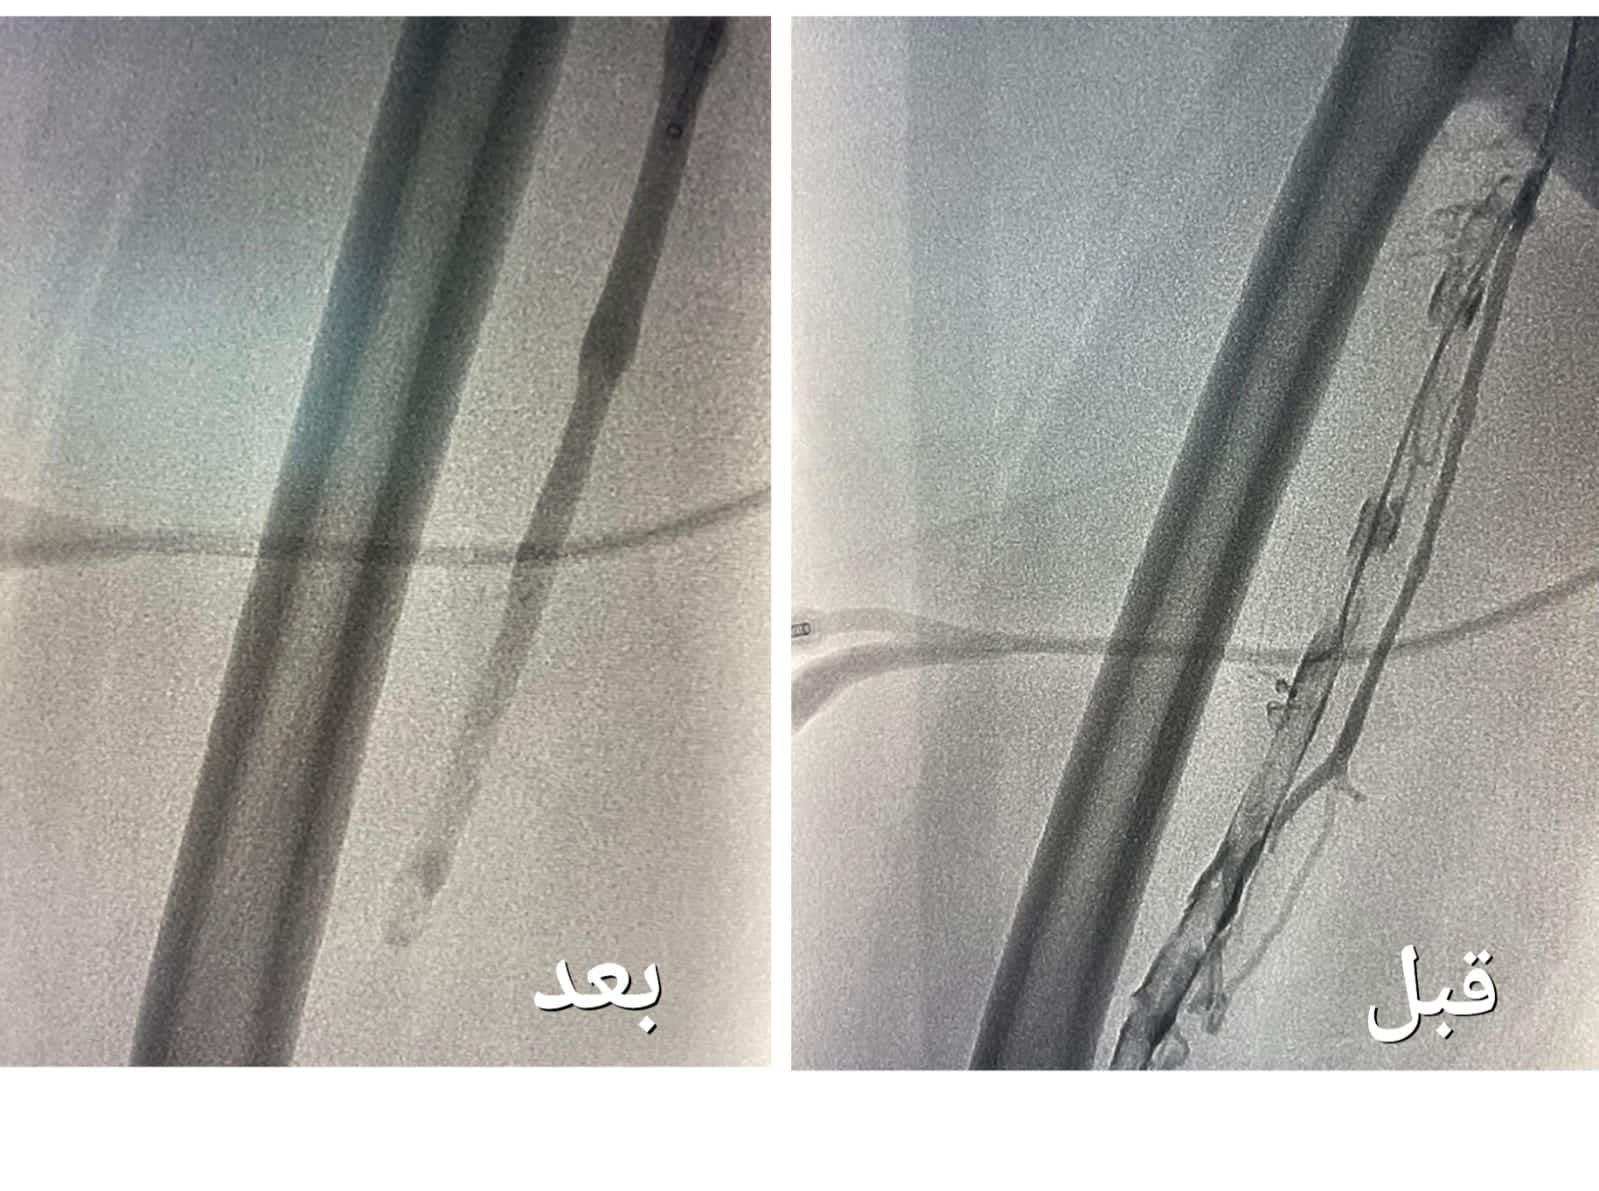

تمكن فريق وحدة الأشعة التداخلية بمجمع الملك عبدالله بجدة من إنهاء معاناة حاجّة هندية تبلغ من العمر ٦٧ عاماً ، و كانت الحاجّة تعاني من جلطة وريدية من مستوى الكاحل إلى مستوى أوردة الحوض الأيمن ، و انتفاخ كامل في القدم مع عدم القدرة على المشي .

وأوضحت "الصحة" أنه بعد  إجراء الفحوصات الطبية و الكشف تبين وجود جلطة وريدية من مستوى الكاحل إلى مستوى أوردة الحوض الأيمن ، و انسداد كامل في أوردة القدم اليمنى حتى الحوض ، قرر بعدها الفريق الطبي تنويم المريضة و التنسيق مع فريق وحدة الأشعة التداخلية بشكل عاجل لدراسة الحالة و معالجتها ،  و وضع الخطة العلاجية ، لنقلها إلى غرف عمليات الأشعة لإجراء عملية بإستخدام جهاز إزالة الجلطات تحت التخدير الموضعي و التهدئة الواعية .

وقالت الوزارة إن العملية

استغرقت نحو ساعتين ، تكللت _ ولله الحمد_ بالنجاح ، تم فيها تركيب فلتر للوريد الأجوف السفلي لمنع انتقال الجلطات للرئة ، و من ثم الدخول للوريد المتجلط في مستوى الكاحل و حقن مواد مذيبة للجلطات ، و قد أستخدمت اجهزة نوعيه لمثل هذه الحالات والتي تعمل على سحب الجلطات بعد إذابتها و توسعة الأوردة بالبالون لإعادة جريان الدم .